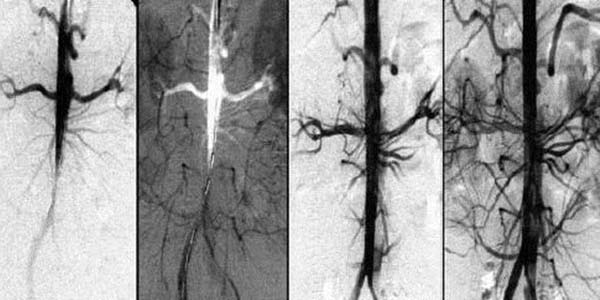

Aby krew lepiej krążyła w naczyniach mózgowych, należy oczyszczać naczynia całego organizmu z nagromadzonych zanieczyszczeń: płytki cholesterolu, skrzepy krwi i wapno wapniowe.

Przywrócenie krążenia krwi i oczyszczenie naczyń krwionośnych to złożony proces. Wpływa na wszystkie naczynia krwionośne organizmu i może poprawić jakość życia.

Działanie składników Bloodease wspiera oczyszczanie naczyń krwionośnych ze złogów płytek cholesterolu, skrzepliny i soli wapnia.

Unikalny skład Bloodease pomaga rozpuszczać blaszki miażdżycowe, skrzepy krwi i wapń. To przyczynia się do zwiększenia światła naczyń krwionośnych, dzięki czemu krew sprawniej krąży w organizmie.